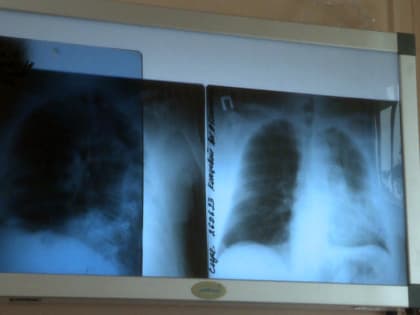

Неделя сохранения здоровья легких проходит в Калужской области

В региональном минздраве рассказали, что с 6 по 12 мая проходит Неделя сохранения здоровья легких в честь Всемирного дня по борьбе с астмой, отмечаемого 7 мая.